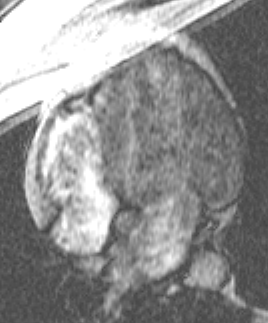

Long axis cine image obtained during suspended respiration

shows dyskinesia of the right ventricular apex.